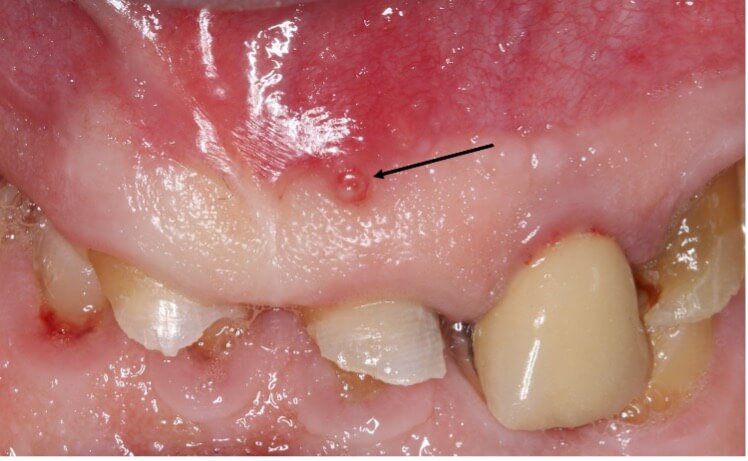

If left untreated, the pulp may become necrotic due to bacterial invasion, potentially resulting in a periapical abscess (Fig. 3). At this point, antibiotic therapy, regularly discussed for misuse in medicine, is often essential alongside surgical interventions such as drainage of the abscess [26]. Once the immediate crisis is addressed, endodontic treatment is necessary to save the affected tooth.

Fig. 3.

Photograph of a gingival fistula (arrow) showing the presence of a periapical abscess abutting the tooth.

The implications of periapical infections are not confined to the mouth; they can act as sources for distant infections, including sinusitis related to dental issues [27] (Fig. 4), infections in prosthetic joints [28], or in rare cases, brain abscesses [29]. According to Deppe et al. [30], oral bacteria may be implicated in approximately 10 to 35% of infective endocarditis cases, highlighting a potential link between oral health and cardiovascular conditions.